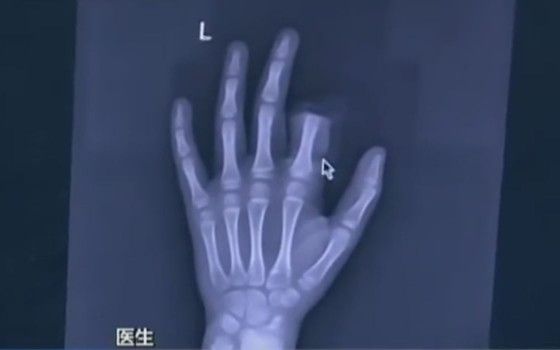

Cele 2 certuri l-au suparat rau pe copil - dupa cel cu tatal sau, s-a ds in bucatarie, a luat un cutit si si-a taiat degetul! Parintii l-au dus de urgenta la spital alaturi de partea sectionata a degetului iar medicii l-au operat timp de 3 ore incercand sa-i reataseze degetul.

Operatia s-a incheiat insa fara succes pentru moment, neputand sa-si foloseasca acel deget. Cu timpul s-ar putea sa redevina functional.